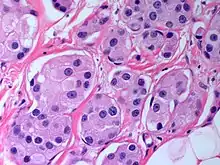

The microscopic histopathology of PACB tumors prepared with hematoxylin and eosin staining shows that >90% of the tumors consist of apocrine gland-like tissue. The lesions must also show that tumor cells have broken through their ducts of origin to invade adjacent tissue in at least one area. Most of the tumor cells (termed type A cells[15]) typically appear somewhat more irregular than normal apocrine gland cells. They have abundant eosinophilic (i.e. pink due to the uptake of the eosin dye) cytoplasm which contain numerous granules[11] and large mitochondria.[15] Their nuclei are large, variably sized and shaped, have multiple nucleoli (which are eosinophilic[11] and may be distinctively large in size[14]), and are surrounded by highly visible nuclear membranes. The cells are arranged into solid sheets, nests, papillae, and/or cords (see Figs. 1 and 2).[11] The tumor cells' cytoplasmic granules test positive when treated with the PAS diastase stain.[16] Binucleated cells, i.e. cells with two nuclei, are common.[10] Less commonly, type B apocrine cells are present; these cells have a more foamy and vacuolated cytoplasm (i.e. containing multiple vacuoles) than type A cells[15] and often resemble foamy histiocytes or sebaceous gland cells.[17] The tumor cells have low to moderate rates of proliferation based on their Ki-67 protein levels.[7] PACB tissues may have localized areas that contain mucin-like secretions within their luminal ducts,[10] localized areas of necrosis (i.e. foci containing dead or dying cells), and/or microcalcifications spotted throughout the apocrine tissue.[11] The stroma (i.e. connective tissue between the sheets, nests, papilla and cords of cells) typically contains non-malignant, infiltrating lymphocytes (see Fig. 3). In an examination of 41 PABC tumors, 33 (80.5%) had <50% of their stroma tissues infiltrated with these cells while 8 (19.5%) had ≥50% of their stroma tissues infiltrated with them. Tumors with ≥50% of their stroma infiltrated with lymphocytes tended to have carcinoma cells that had high rates of proliferation.[11] Metastatic and recurrent PACB tumors have a histopathology similar to their original primary tumors.[14]